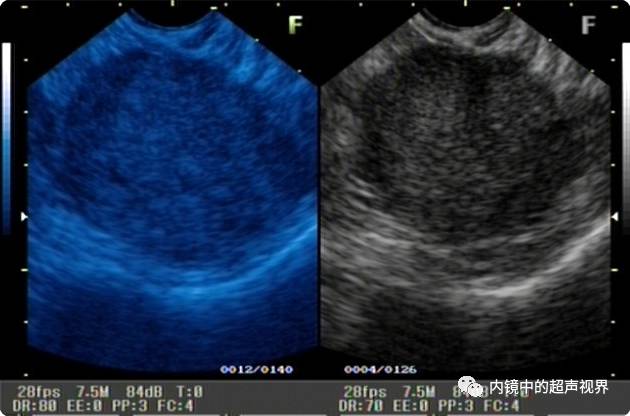

我现在使用的超声内镜DR可调节范围为30-90。以下三张图片显示的是同一个胰头肿物,肿物回声与胰腺回声非常接近,DR分别为90、70、40,其它参数相同,您更喜欢哪一张。